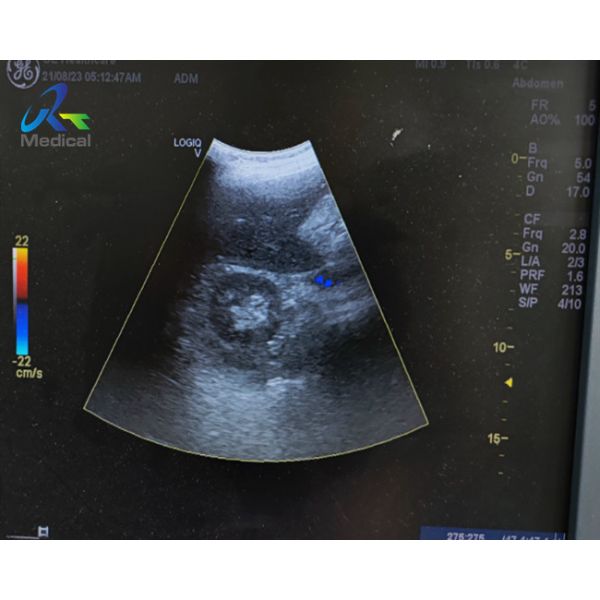

GE 4C-RS Convex Probe Ultrasound Transducer Lens Replacement

Fault Phenomenon: The cable is deformed, the image on the machine has dark shadow, and the lens is completely blistered.

Suggestion: Repair the lens(Lens completely blistered image missing could not be determined, confirming the image of matching layer on the machine while replace the lens.)

Picture